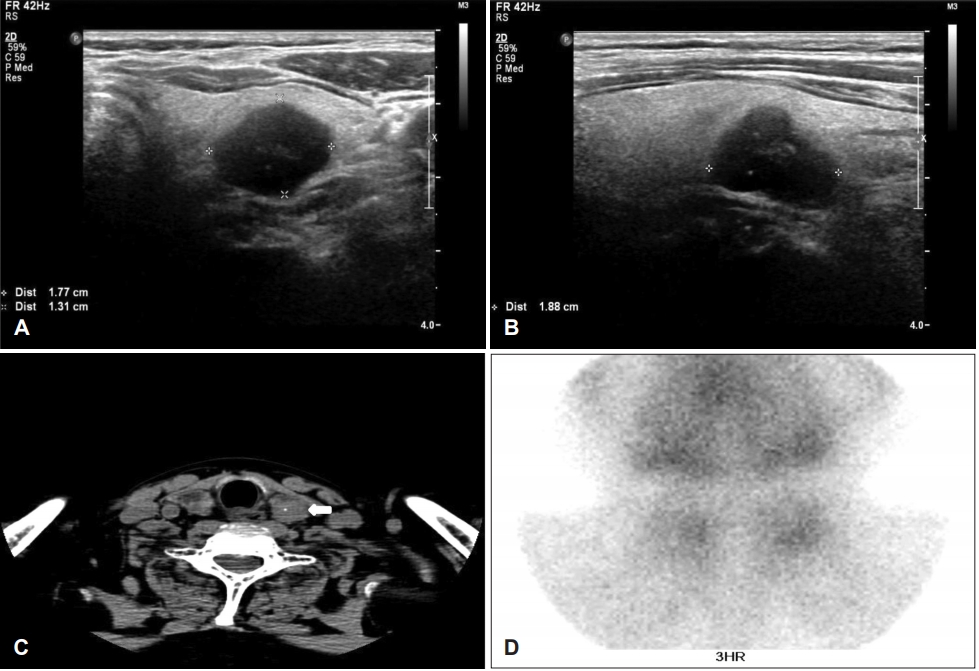

증 례59세 남자 환자가 좌측 갑상선 결절의 초음파 유도하 세침흡인검사에서 베데스다 분류 III 또는 IV로 평가되어, 진단적 수술을 위해 내분비내과에서 의뢰되었다. 기저질환으로 당뇨, 만성 신부전, 부신 기능 저하증 및 부갑상선 항진증 등이 있었다. 경부에 비정상적으로 촉지되는 종물은 없었고, 신경학적 검사에서도 정상 소견이었다. 갑상선 초음파에서 좌측 갑상선의 중간에 고형의 1.7×1.8 cm 크기의 저에코성 종물이 관찰되었다(Fig. 1A and B). 비조영증강 경부 전산화단층촬영에서 좌측 갑상선의 중간 부위에 석회화를 동반한 타원형의 2.1×1.9 cm 크기의 종물이 관찰되었다(Fig. 1C). 갑상선 기능검사, 총 칼슘 및 이온화 칼슘, 인, 마그네슘 및 알부민 등은 모두 정상 범위였으나, 부갑상선 호르몬(intact parathyroid hormone, iPTH)은 228 pg/mL(참고값: 15~65)로 크게 증가된 소견이었다. 혈중요소질소는 55 mg/dL(참고값: 8~24), 크레아티닌 2.9 mg/dL(참고값: 0.6~1.0), 사구체여과율(estimated glomerular filtration rate)은 6 mL/min/1.73 m2 (참고값: 60 이상) 등으로 만성 신부전에 합당한 소견이었다. 부갑상선의 기능 평가를 위하여 시행한 99mTc-sestamibi 스캔에서는 특이 소견 없었다(Fig. 1D).

NotesAuthor Contribution Conceptualization: Seung Woo Kim. Data curation: Seong Kyu Moon. Formal analysis: Beom Mo Koo. Investigation: Beom Mo Koo. Methodology: Seong Kyu Moon. Supervision: Seung Woo Kim. Validation: Mi Ji Lee. Visualization: Mi Ji Lee. Writing—original draft: Beom Mo Koo, Seung Woo Kim. Writing—review & editing: Seung Woo Kim. Fig. 1.Preoperative imaging studies. Transverse scans of neck ultrasonography show hypoechoic nodules, 1.7×1.3×1.8 cm sized mass on posterior aspect of left thyroid gland (A) and (B) (asterisks), and the non-enhanced axial neck CT scans show 2.1×1.9 cm sized ovoid mass including calcification (arrow) (C), and the three hours’ image of 99mTc-sestamibi scan shows no abnormal finding (D). Fig. 2.The photo of the extract immediately after surgery. The black circled area of left thyroid means intrathyroidal parathyroid carcinoma, and two black arrows show right superior and inferior parathyroid hyperplasia. Fig. 3.The gross specimens. (A) is extracted left thyroid gland and the intrathyroidal mass is marked with a black circle. (B) is horizontal cutting at mid-level of left thyroid (black circled portion), and it shows pale yellowish and firm mass. (C) is right upper parathyroid mass. Fig. 4.The pathological findings. The tumor shows solid growth pattern and invades adjacent thyroidal parenchyma (arrows, H&E, ×25) (A). Due to uniform tumor cells with colloid-like material, it is difficult to differentiate between follicular thyroid neoplasm and parathyroid neoplasm based on the histology (H&E, ×200) (B). It shows contralateral parathyroid hyperplasia (H&E, ×25) (C). The immunohistochemical findings. The tumor cells are negative for thyroglobulin (D) and thyroid transcription factor-1 (E), which suggest non-thyroidal origin tumor. And the immunopositivity for cytokeratin 7 (F) and GATA-3 (G) support that the tumor is parathyroid neoplasm (×200) (D-G). H&E: hematoxylin and eosin. REFERENCES1. Wynne AG, van Heerden J, Carney JA, Fitzpatrick LA. Parathyroid carcinoma: Clinical and pathologic features in 43 patients. Medicine (Baltimore) 1992;71(4):197-205.